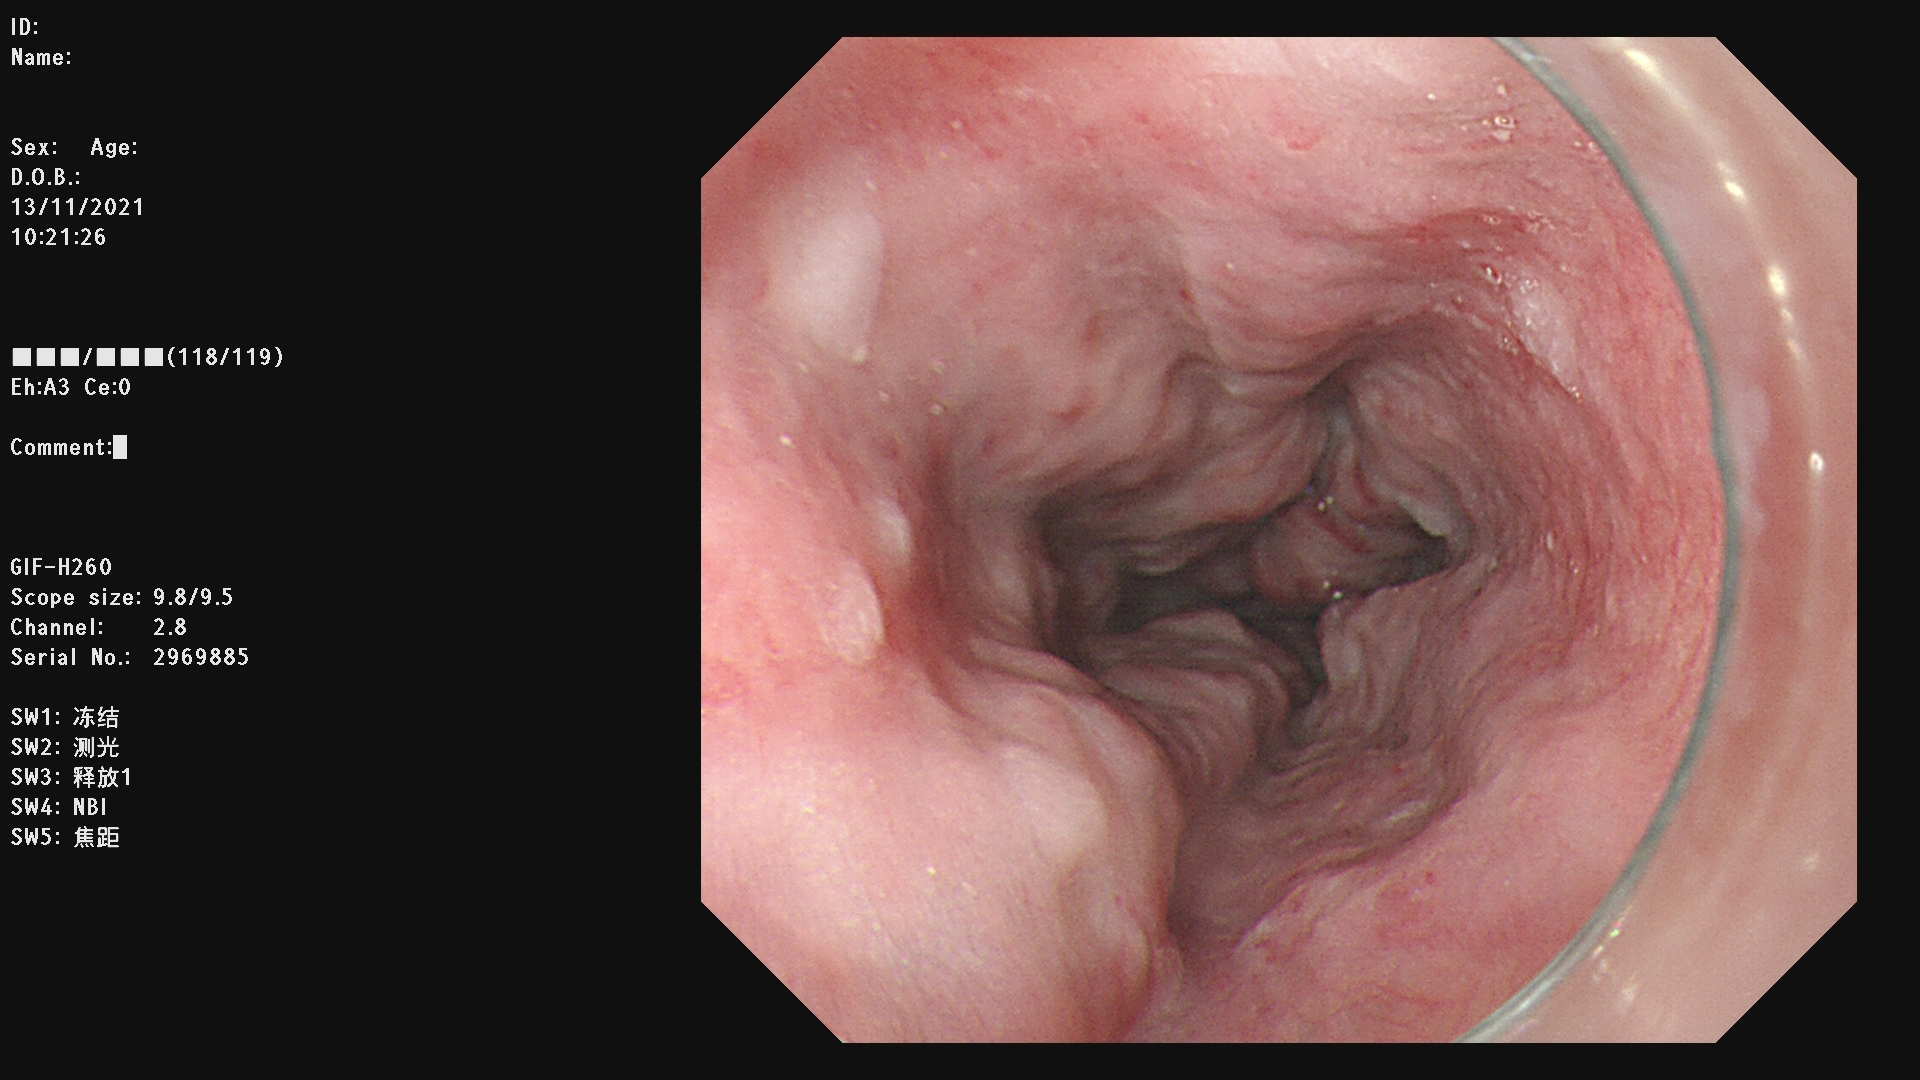

食管胃静脉曲张破裂出血(esophagogastric variceal bleeding,EVB)具有发病迅速、病死率高的特点。内镜下食管胃底静脉曲张治疗术是经内镜用套扎方法或药物治疗食管胃底静脉曲张的方法。目前内镜下治疗主要包括内镜下食管静脉曲张套扎术( endoscopic variceal ligation,EVL)与内镜下食管胃底静脉曲张硬化术( endoscopic injection sclerotherapy,EIS)。

内镜下食管静脉曲张套扎术简称EVL,是一种安全有效的治疗食管静脉曲张破裂出血以及预防出血的方法。EVL具有操作简便、创伤小、安全性高,疗效确切、可重复进行的优点。

例一 :